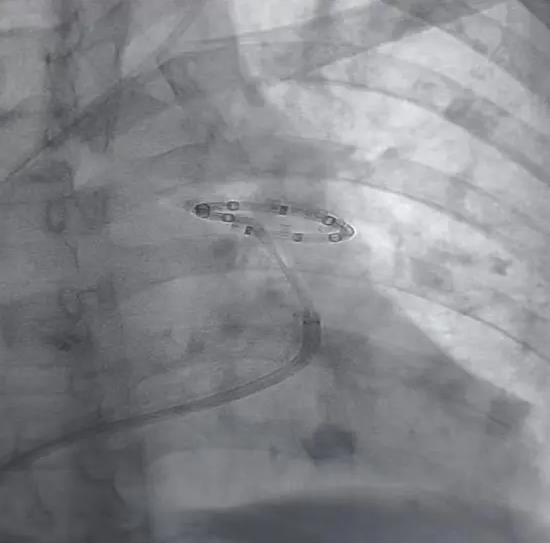

该技术通过股静脉穿刺微创入路,在数字减影血管造影(DSA)精准引导下,将射频消融导管送至肺动脉主干,定位并消融肺动脉周围过度激活的交感神经,阻断异常神经信号传导,从而降低肺动脉压力、降低肺血管阻力、改善心功能、提升运动耐力,实现 “一次手术、长期获益”。

手术成功:术后即刻见效 患者重获 “心” 生

在我院心脏外科团队默契配合下,手术顺利完成。术后即刻复查发现,患者肺动脉收缩压显著下降,胸闷、气短症状明显缓解,生命体征平稳。目前患者术后监护恢复良好,各项指标持续改善,活动能力较术前显著提升。